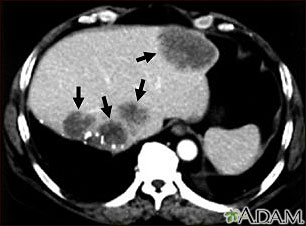

The abdominal CT scan may show some cancers, including:

- Cancer of the renal pelvis or ureter

- Colon cancer

- Hepatocellular carcinoma

- Lymphoma

- Melanoma

- Ovarian cancer

- Pancreatic cancer

- Pheochromocytoma

- Renal cell carcinoma (kidney cancer)

- Spread of cancers that began outside the belly

The abdominal CT scan may show problems with the gallbladder, liver, or pancreas, including:

- Acute cholecystitis

- Alcoholic liver disease

- Cholelithiasis

- Pancreatic abscess

- Pancreatic pseudocyst

- Pancreatitis

- Blockage of bile ducts